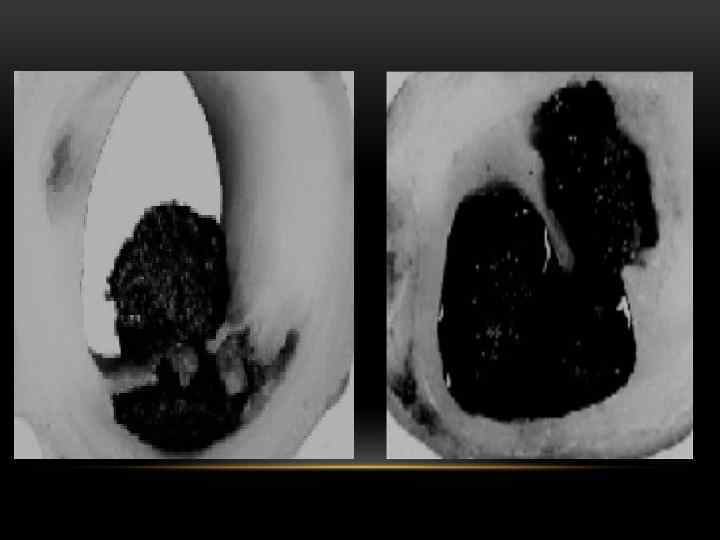

ЭТИОЛОГИЯ • Разрыв (трещина, эрозия) нестабильной АСБ с последующим атеротромбозом.

МЕХАНИЗМЫ РАЗРЫВА АТЕРОСКЛЕРОТИЧЕСКОЙ БЛЯШКИ • АКТИВНЫЙ РАЗРЫВ (связан с секрецией макрофагами протеолитических энзимов – металлопротеиназ, которые истончают фиброзное покрытие бляшки) • ПАССИВНОЕ РАЗРУШЕНИЕ механического воздействия) (вследствие

ДРУГИЕ ПРИЧИНЫ (РЕДКО) • Кровоизлияние в АСБ без ее разрыва. • Изолированный спазм КА. • Диссекция КА. • Эмболия КА. • Артериит. • Врожденная патология сосудов. • Расслоение восходящего отдела аорты с вовлечением КА. • Причины, не связанные с КА.

ПАТОГЕНЕЗ ТРОМБ ПРИСТЕНОЧН ЫЙ «белый» ОКС без подъема ST ОБТУРИРУЮЩ ИЙ «красный» ЭМБО Л ОКС с подъемом ST